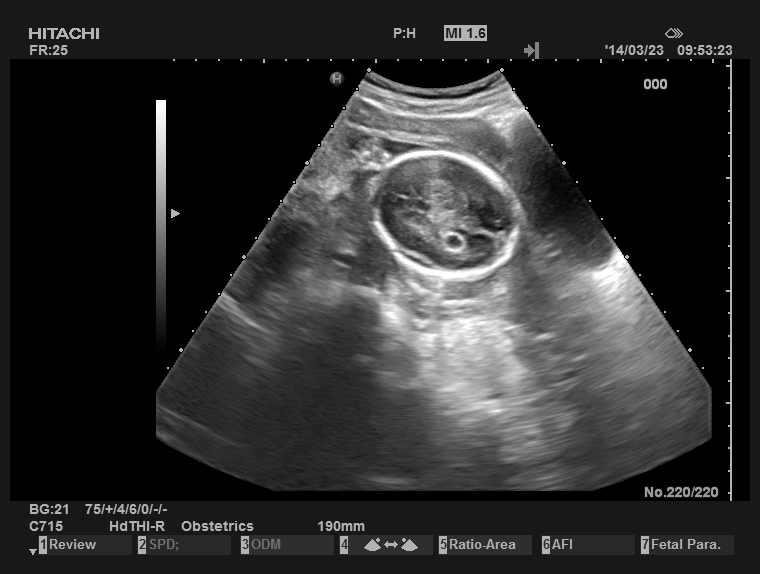

超声入门贴979中孕胎儿脉络丛囊肿

图片尺寸560x420